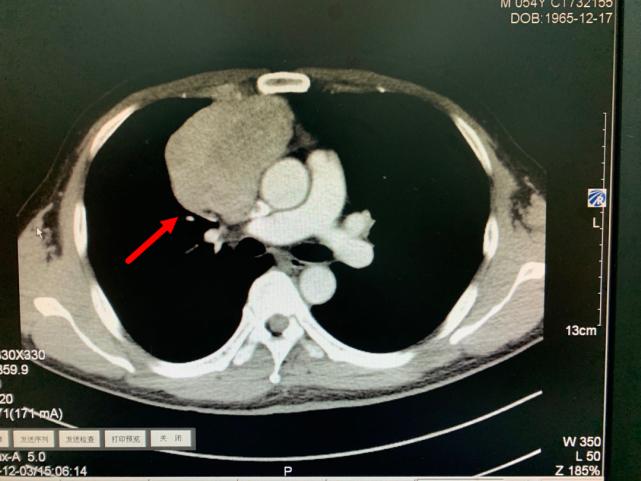

箭头所指为巨大纵隔肿瘤

今年11月份,老方因“肠炎”在浙江省立同德医院肛肠科住院。“新冠”期间住院需要常规做胸部CT筛查,检查出来的结果却让他和医生们大吃一惊,胸部CT显示:胸腔内存在一个巨大肿瘤即纵膈肿瘤,大小约10.0cm×6.5cm×7.0cm,大小和一个成人男性拳头差不多。肿瘤紧靠着肺部、心脏及大血管,且与部分大血管有粘连,对重要的脏器已经造成了挤压。在确定胃肠道没有严重病患后,老方被转入心胸外科进一步作检查、治疗。

肿瘤与周围血管存在黏连